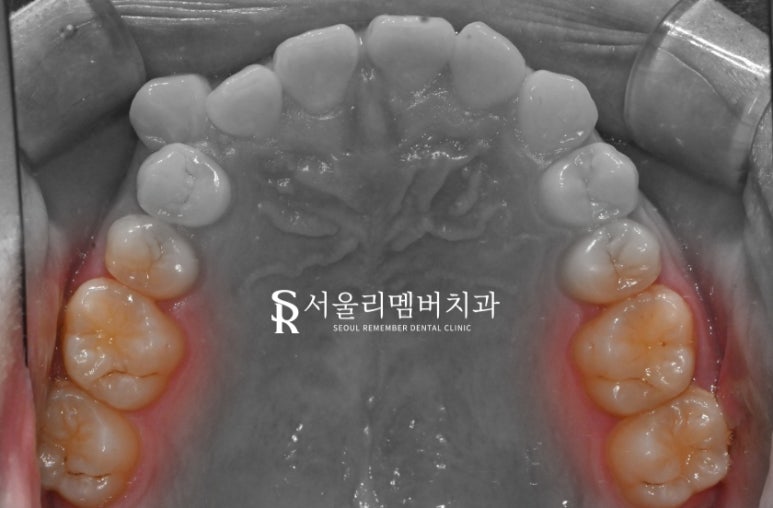

위 사진에서 알 수 있듯이

양쪽 큰어금니 쪽 사진에 보면

다발성으로 있는 것을 볼 수 있습니다.